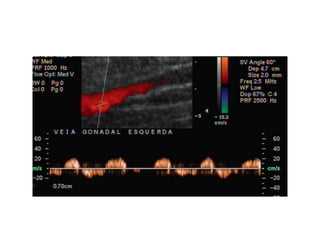

Refluxo  de  veia  Gonadal  com  formação   varicosa  ao  lado  do  ovário

Comment  établir  le  diagnos=que  ?   1.  Par   la   symptomatologie,   en   par8culier   la   douleur  et  la  lourdeur  dans  le  bassin  avec  une   aggrava8on   pendant   la   menstrua8on,   mais   aussi   la   dysménorrhée,   la   dyspareunie,   la   cons8pa8on  et  les  douleurs  lombaires.   2.  Par   la   présence   de   varices   dans   la   région   postérieure   et   latérale   des   cuisses,   dans   les   fessiers  et  les  par=es  génitales.   3.  À   l’aide   d’un   écho-­‐doppler   transvaginal   et   abdominal.